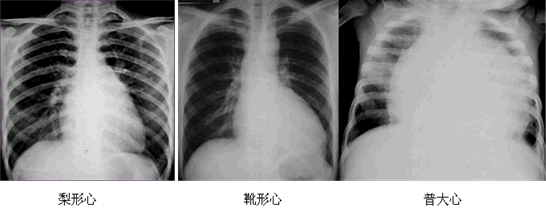

| X線 | 心界增大 | 常見疾病 | |

| 二尖瓣型 | 梨形心 | 左心房增大 | 二尖瓣狹窄(最常見) |

| 主動脈型 | 靴形心 | 左心室擴大 | 法洛四聯(lián)征、主動脈瓣膜疾病、高血壓心臟病等 |

| 普大型 | 普大心 | 心界向兩側(cè)擴大 | 心肌病、心臟病后期、心包積液等 |